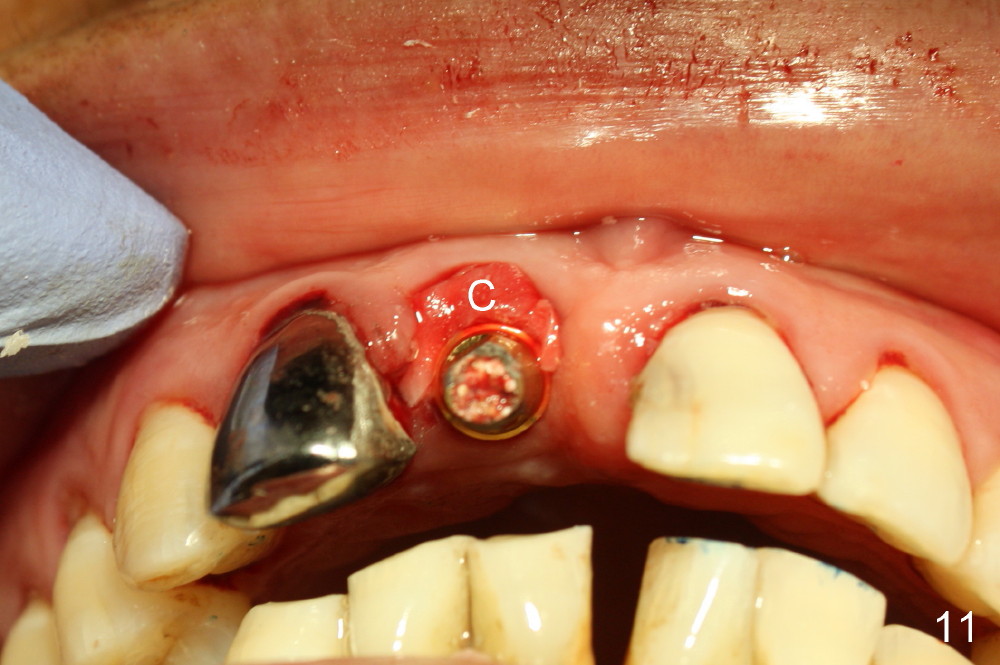

A 64-year-old lady requests replacing #7 and 8 crowns (Fig.1,2). When #8 is extracted, the labial plate is found to be missing (Fig.3). Following 2 mm pilot drill (Fig.4,5 P), 3.8 mm tap drill (Fig.6,7 T) and 4.5x14 mm implant (Fig.8 I) and 4.8 mm abutment (Fig.9 A), corticocancellous bone is harvested from the left tuberosity and placed in the labial gap of the socket (Fig.10 G). Collagen dressing is placed over the bone graft (Fig.11 C). The former is secured in place by an immediate provisional (P).

The autogenous bone graft from the tuberosity is mainly cancellous. It consists of small pieces. They are easily packed into the labial gap. The small portion of the cortical bone provides meshwork and may retard resorption.